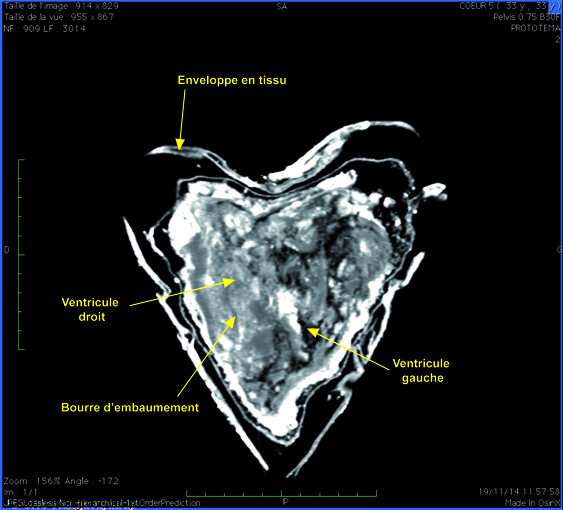

La qualité de conservation du corps permit de reconstruire une personne, une personnalité, et de récolter des informations qui échappent habituellement aux scientifiques en raison de la dégradation des éléments organiques, telles les plantes nécessaires à l’embaumement souvent impossibles à analyser. L’autopsie virtuelle a notamment permise une vision complète de l’ensemble du corps : les os, les tissus, les pathologies. « Louise avait des calculs rénaux assez importants », précise le docteur Fabrice Dedouit, spécialiste de l’autopsie virtuelle. Et de poursuivre : « Nous sommes dans un autre archéologie. L’analyse de tissus mous, d’organes est une grande première en archéologie ».

Premier examen tomodensitométrique du corps habillé de Louise de Quengo